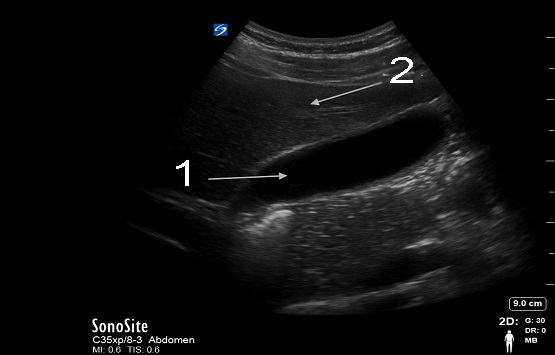

Gallbladder Sagittal with Liver Image

Gallbladder

Liver